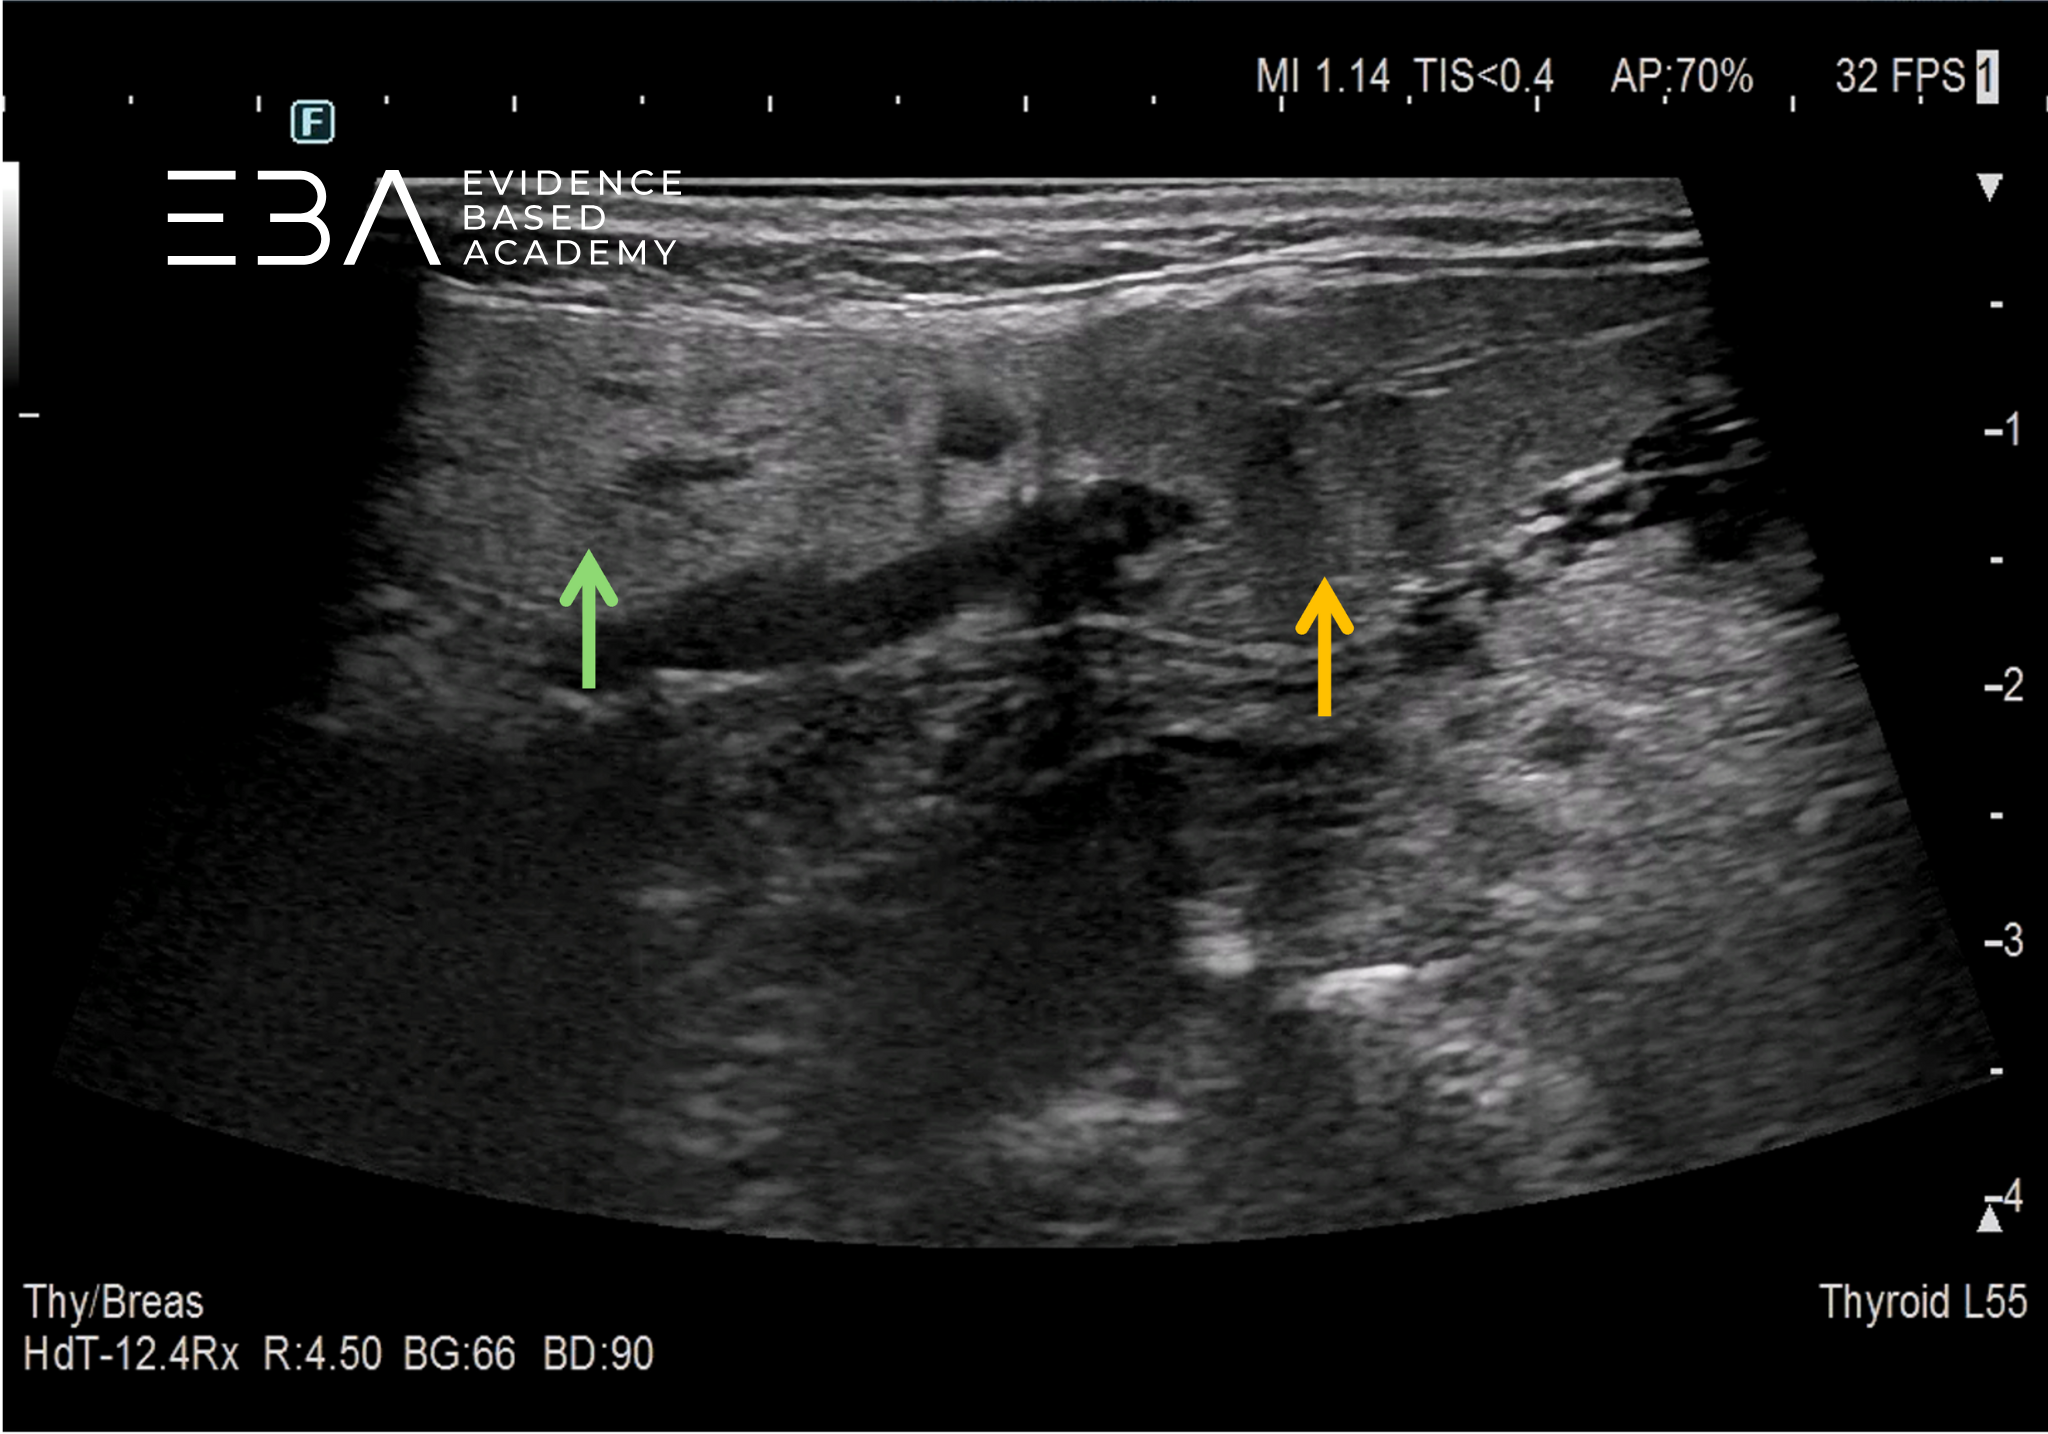

8. Prawidłowy obraz ślinianki przyusznej i ślinianki podżuchwowej.

USG ślinianki charakteryzują się echogenicznością wyższą od echogeniczności mięśni (zbliżoną do echogeniczności tkanki tłuszczowej oraz echogeniczności prawidłowego miąższu tarczycy) i jednorodną echostrukturą. W warunkach prawidłowych przewody wyprowadzające zazwyczaj są niewidoczne. Echogeniczność ślinianki podżuchwowej może być nieco niższa od echogeniczności ślinianki przyusznej. Unaczynienie prawidłowych ślinianek jest skąpe, a w przypadku ślinianek podjęzykowych często trudne do uwidocznienia.